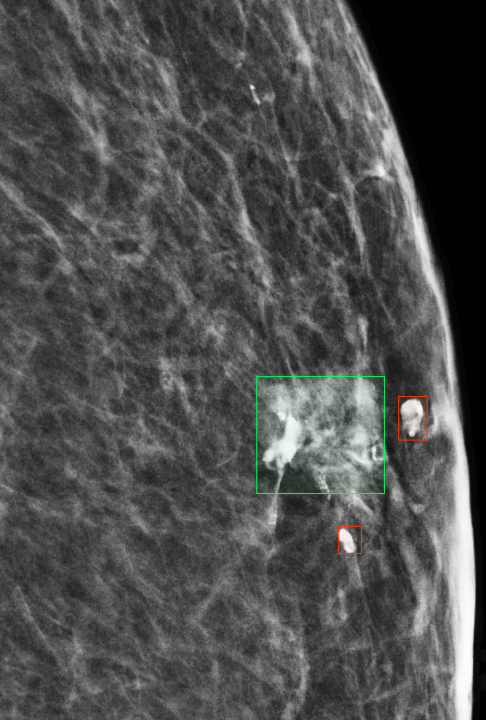

4.6 Anomaly Segmentation

The InBreast dataset was used to evaluate the anomaly segmentation performance. The evaluation scenario is basically zero-shot, as the images tested on are different from those used to train MAMBO on. To allow comparison with existing approaches used in the domain of radiology, only the low-resolution (global context) model was used as described in Sec. 3 and trained on the subset of healthy images taken from the VinDr dataset.

To select the optimal value of the timestep parameter () for the anomaly segmentation task, values in the range were evaluated. The optimal value of , was obtained for all masses in the dataset, corresponding to an IoU of 0.216.

To further probe the capabilities of recognizing lesions of different sizes, Tab. 6 illustrates the performance of MAMBO using the optimal . To produce the data, lesions are grouped in buckets according to size. The size of lesions (in pixels) in the dataset follows an exponential distribution. Lesions are assigned to the buckets using a logarithmic scale, which yields buckets with the same number of images (18) in each, except for the last bucket, which contains 17 images.

| Area (px) | 64 | 128 | 222 | 521 | 951 | 2187 |

|---|---|---|---|---|---|---|

| IoU | 0.019 | 0.069 | 0.125 | 0.280 | 0.423 | 0.393 |

| Area is represented on a log scale, median size is shown for each bucket. | ||||||

As Tab. 6 shows, larger lesions are easier to detect using the model. Exceptions occur when a lesion grows large, nearing breast size, and the model finds it difficult to remove the whole anomaly. Quantitatively, the best result achieved by the proposed approach is as high as , a significant improvement over the reported for AnoDDPM in [44] for brain radiology images.

Figure 10 shows additional results of anomaly segmentation on the InBreast dataset, using the MAMBO low-resolution (global-context) model, for the size of lesion that the approach detects well, as well as one which is challenging for it.